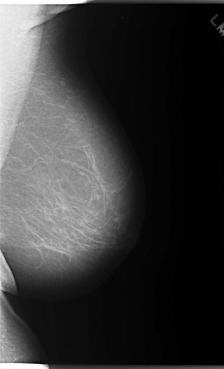

C_0086_1.RIGHT_MLO

FILE: C_0086_1.RIGHT_MLO.OVERLAY

TOTAL_ABNORMALITIES 1

ABNORMALITY 1

LESION_TYPE MASS SHAPE LOBULATED MARGINS MICROLOBULATED

ASSESSMENT 5

SUBTLETY 5

PATHOLOGY MALIGNANT